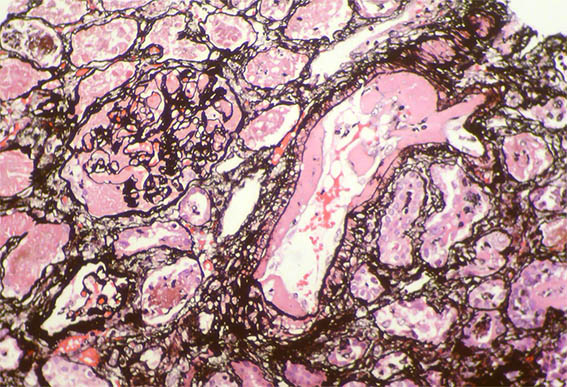

Figure 10. Methenamine-silver stain, X400. Note the artery and the glomerulus.